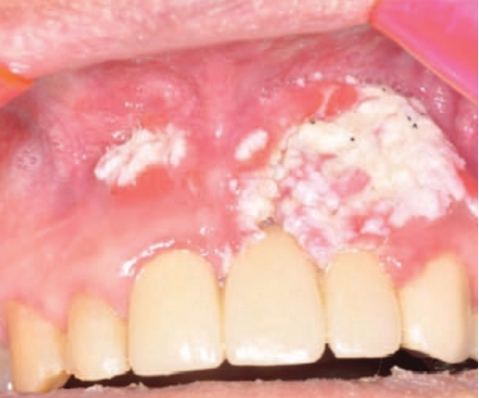

이상과 같이 흡연이라는 유해 요소적문제를 갖고 있는 환자에게 폐암이나 자궁암, 위암, 구강암 등이 발병하는 경우에는 발암물질로 작용하는 다이옥신수용체들의 상대적 수준이나 활성도, 그리고 그에 대한 외인성 리갠드의 수나 활성도가 제공되는 담배연기로 인한 환경적 영향(ETS 노출을 포함)에 의해서 나타나는것임을 알 수 있다. 담배연기의 한 성분인 타르에 포함된 수많은 성분중 aryl hydrocarbon, 즉 TCD D(dioxin)와 같은 발암 인자는 구강암, 폐암, 후두암, 식도암, 위암, 췌장암, 신장암, 방광암, 자궁암을 비롯한 각종 암을 유발한다.

우리나라에서 암으로 사망하는 비율은 전체 사망자의 20%가 넘는데 암으로 인한 사망자 세사람중 한 명은 흡연에 의한 것이다. 특히 우리나라에서 장기적인 흡연자가 폐암에 걸려 사망할 확률은 담배를 피우지 않는 사람보다 남자의 경우는 22배나 높고 여자에게서는 12배가 높다. 또한 흡연은 치과영역에서 주로 발견되는 구강암의 발생확률을 적게는 6배에서부터 최고 18배이상까지 상승시킨다.

미국에서 흡연으로 인한 구강암으로 사망하는 사람이 매년 8,000명을 상회하는 것으로 나타났다. 위암이나 식도암, 후두암에 걸릴 확률도 비흡연자보다 1.7~6.4배나 높게 나타난다. 췌장암에 걸려 사망하는 확률이 다섯 배, 방광암에 걸려 사망할 확률도 비흡연자보다 네 배나 더 높다. 자궁경부암이나 난소암, 신장암의 발생율도 크게 높아 진다. 같은 흡연자라 할지라도 흡연기간은 가장 중요한 발암의 원인이다. 즉 흡연기간이 길면 그만큼 암에 걸릴 확률이 높아진다.